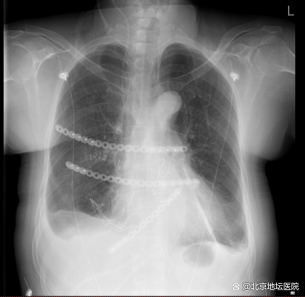

术后影像检查

在胸外科医护团队精心的治疗和照顾下,张阿姨术后恢复顺利,术后第一天就下床活动了,复查胸片提示胸廓重建效果好,肺复张良好。